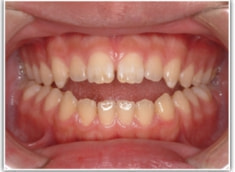

開咬(かいこう:オープンバイト)ケース

治療法:表の矯正(T21ブラケット)

(インプラントアンカーや外科矯正は行わず、エラスティックと機能訓練のみ)

治療前